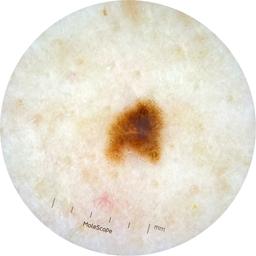

ISIC_6476310

2001 x 2001

acquisition_day 463

age_approx 40

anatom_site_1 Trunk

anatom_site_2 Anterior trunk

anatom_site_general anterior torso

diagnosis_1 Benign

diagnosis_confirm_type single image expert consensus

image_type dermoscopic